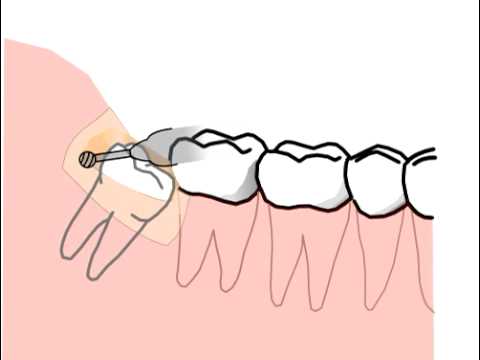

I problemi ai denti del giudizio con nervi infiammati si verificano in genere quando i denti sono impattati, cioè non emergono completamente dalla gengiva. Questo può accadere quando non c’è abbastanza spazio nella mascella per accogliere la crescita dei denti, o quando i denti emergono con un angolo che li porta a premere contro i denti o l’osso circostanti. Quando i denti del giudizio sono impattati, si può creare uno spazio tra la gengiva e il dente, che può diventare un terreno fertile per i batteri. Questo può portare a un’infezione, che può poi causare l’infiammazione del nervo.

Nei casi più gravi, il chirurgo orale può consigliare una procedura chirurgica per rimuovere i denti del giudizio impattati. Questa procedura viene generalmente eseguita in anestesia locale e prevede un’incisione nella gengiva per accedere al dente interessato. Il chirurgo maxillo facciale rimuoverà quindi con cura il dente e il tessuto circostante per assicurarsi che tutta l’infezione venga rimossa. Una volta rimosso il dente, il dentista può prescrivere farmaci antidolorifici e antibiotici per gestire il disagio e prevenire l’infezione.